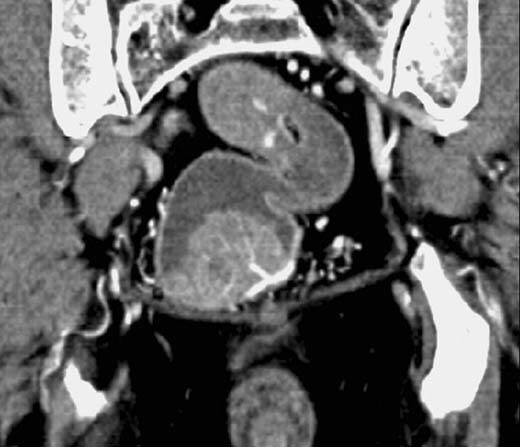

CT nach rektaler Füllung mit Wasser (negatives Kontrastmittel) und i.v.

Kontrastmittel.

Breitbasige sessile

Raumforderung bzw. Kontrastmittel-Aussparung des Rektums.

Rektum-Karzinom